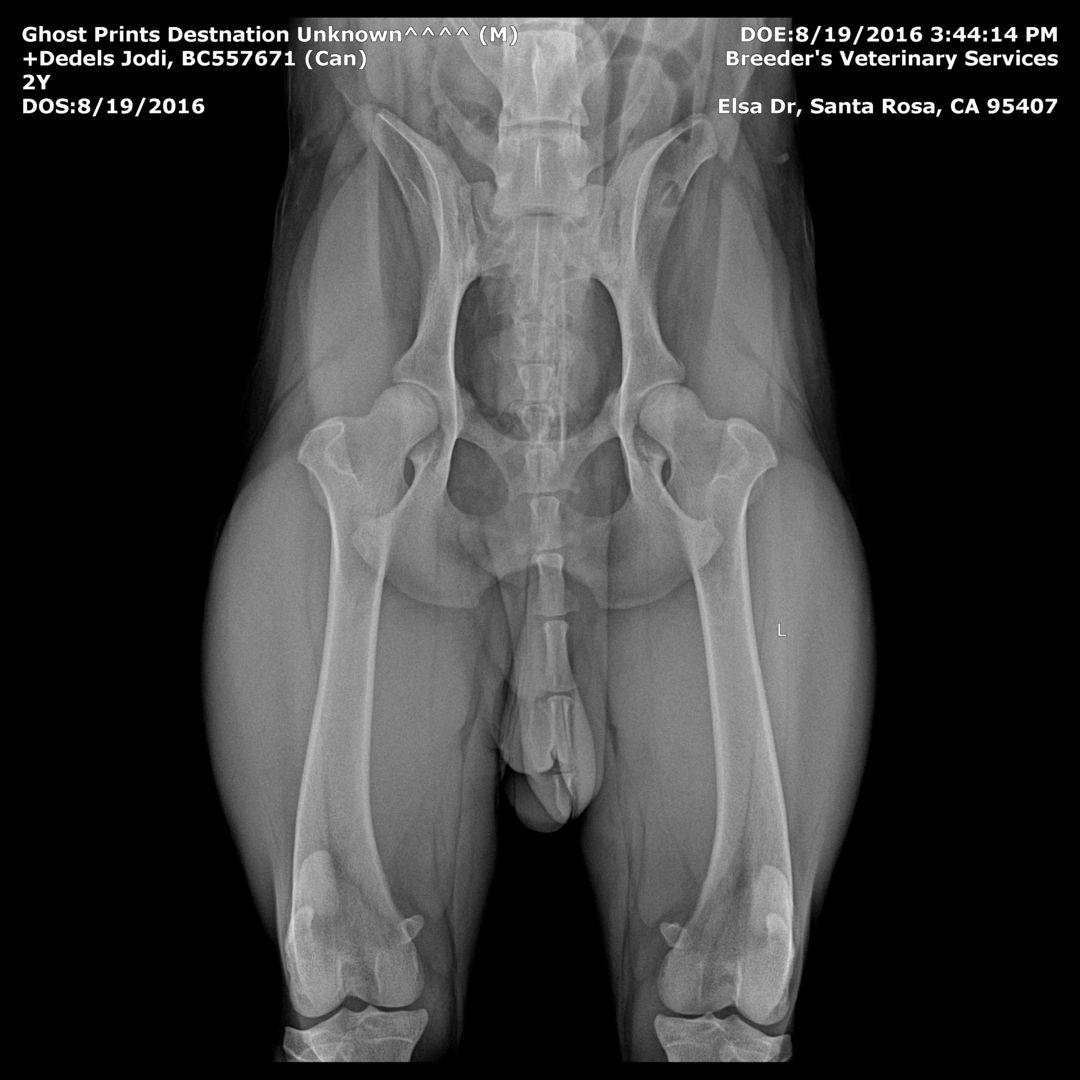

Hips: Good